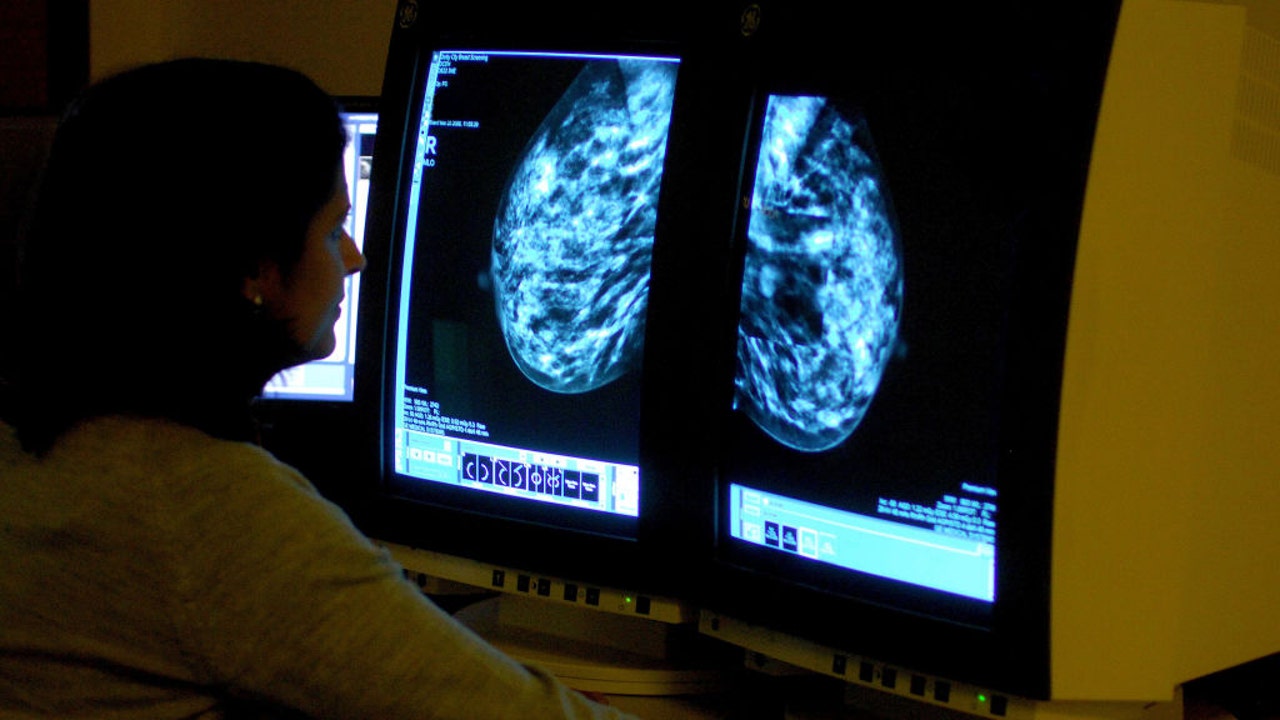

FILE - A file image shows a consultant analyzing a mammogram showing a womans breast in order check for breast cancer. (Photo by Rui Vieira - PA Images/PA Images via Getty Images)

Oncologists in the U.K. have developed an AI model to help predict whether aggressive forms of breast cancer will spread based on changes in a patient’s lymph nodes.

Researchers behind last week’s study hope that by using AI to analyze the immune response in the lymph nodes of women with triple-negative breast cancer, they can better gauge how likely the disease will spread.